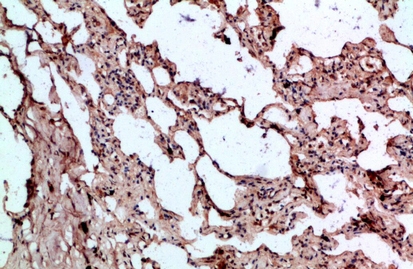

IHC (Immunohistochemisry)

(Immunohistochemical analysis of paraffin-embedded human-lung, antibody was diluted at 1:200)